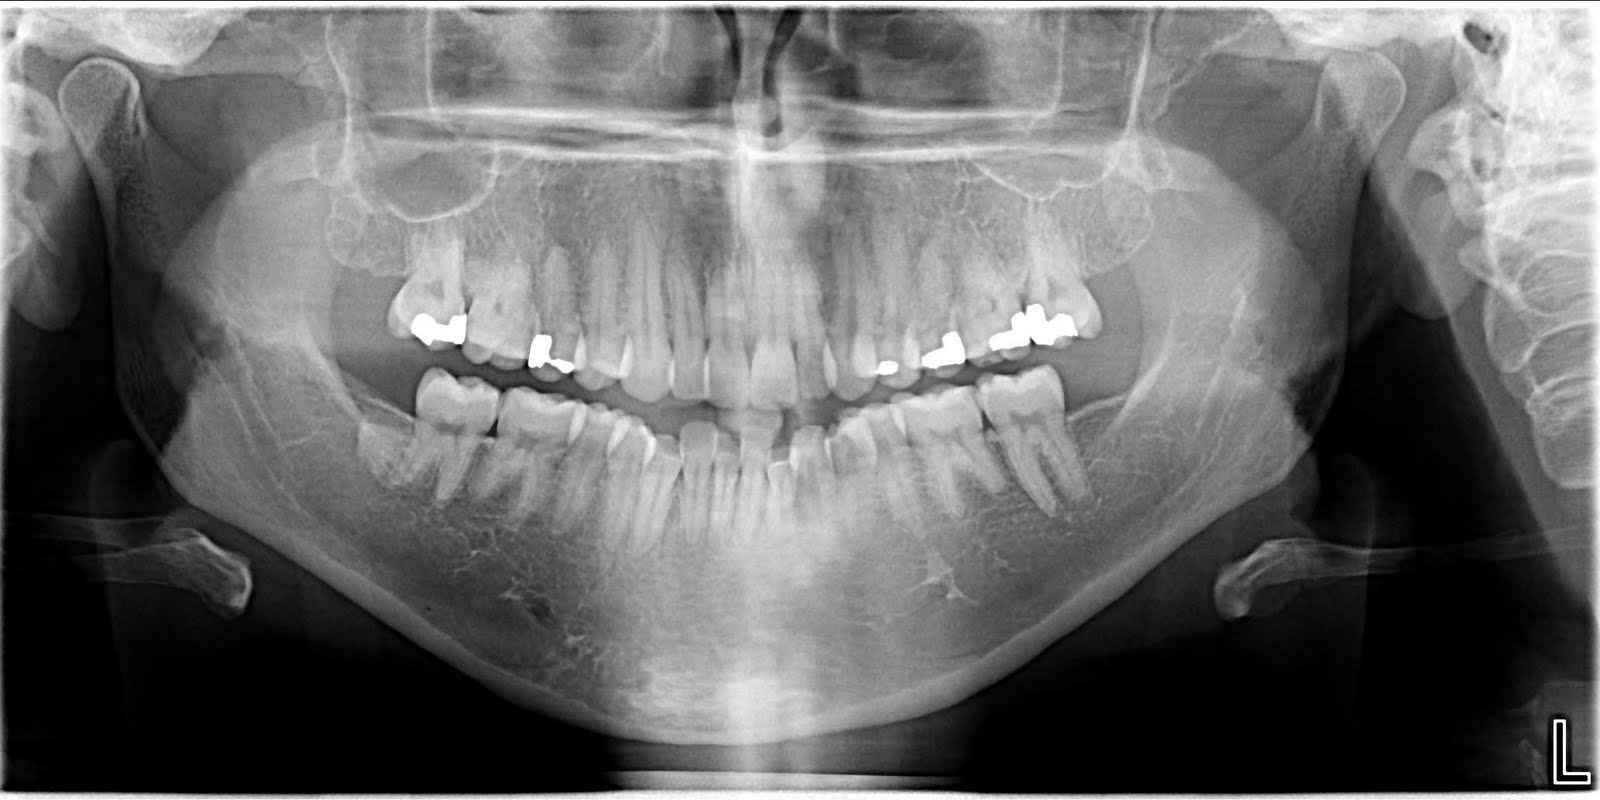

Jaw X Ray Positioning . The temporomandibular joint (tmj) is an atypical synovial joint located between the condylar process of the mandible and the mandibular fossa and articular eminence of the temporal. Utilizes specific views like panoramic and lateral oblique to diagnose jaw and dental conditions accurately. Although panoramic radiographs are limited by distortion and frequent positioning errors, they are adequate in identifying the. The head is first placed in a true lateral position. Interpupillary line (ipl) perpendicular and midsagittal plane (msp) parallel to the detector. Find the best radiology school and career information at www.rtstudents.com.

Although panoramic radiographs are limited by distortion and frequent positioning errors, they are adequate in identifying the. Interpupillary line (ipl) perpendicular and midsagittal plane (msp) parallel to the detector. The temporomandibular joint (tmj) is an atypical synovial joint located between the condylar process of the mandible and the mandibular fossa and articular eminence of the temporal. The head is first placed in a true lateral position. Find the best radiology school and career information at www.rtstudents.com. Utilizes specific views like panoramic and lateral oblique to diagnose jaw and dental conditions accurately.